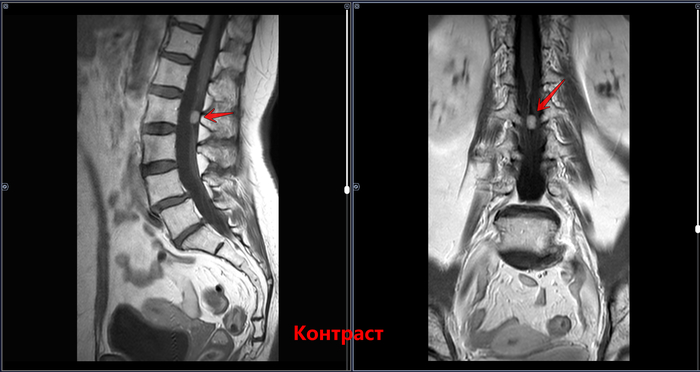

МРТ возрастной пациентки, поясничного отдела позвоночника с контрастным усилением, жалобами на боль в пояснице с иррадиацией в левую нижнюю конечность

Интрадурально на уровне тела L2 позвонка визуализируется патологическое образование, овальной формы, с четкими ровными контурами, неоднородной структуры, характеризующееся преимущественно изогиперинтенсивным МР-сигналом на Т2-ВИ и изо- на Т1-ВИ. После внутривенного введения парамагнитного контрастного вещества отмечается его равномерное накопление образованием, размером до 13х8х7 мм . Других участков патологического накопления не определяется .Определяется смещение тела L4 позвонка кпереди относительно тела L5 позвонка на 3,5 мм. В L4-L5 определяется дорзальная протрузия межпозвонкового диска размером 2.6мм. В L5-S1 определяется дорзальная левосторонняя фораменальная протрузия диска размером 3 мм. Дегенеративно-дистрофические изменения.

МР-картина интрадурального объемного образования на уровне тела L2 позвонка (соответствует невриноме). МР-картина дегенеративно-дистрофических изменений пояснично-крестцового отдела позвоночника. Антесподилолистез L4-L5. Протрузии дисков L4-L5, L5-S1.